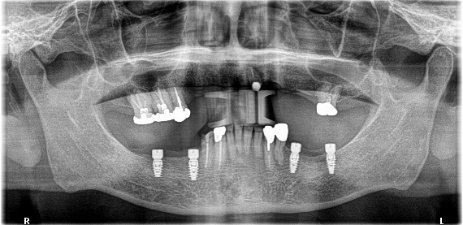

Before

※赤丸は、歯根が破折していたため抜歯しました

※黄色丸は、2006年10月に埋入したインプラント

After

※緑丸は、今回埋入したインプラント

左上第二小臼歯と第一大臼歯の歯根が破折していたため、保存することができず抜歯しました。第一小臼歯は、すでにありませんでしたので、2本抜歯後3本欠損のところにインプラントを2本埋入しました。

所感

2006年10月に右下と左下の欠損部分にインプラント治療をしました。今回も左上の歯を失ったところは、インプラント治療を希望されました。